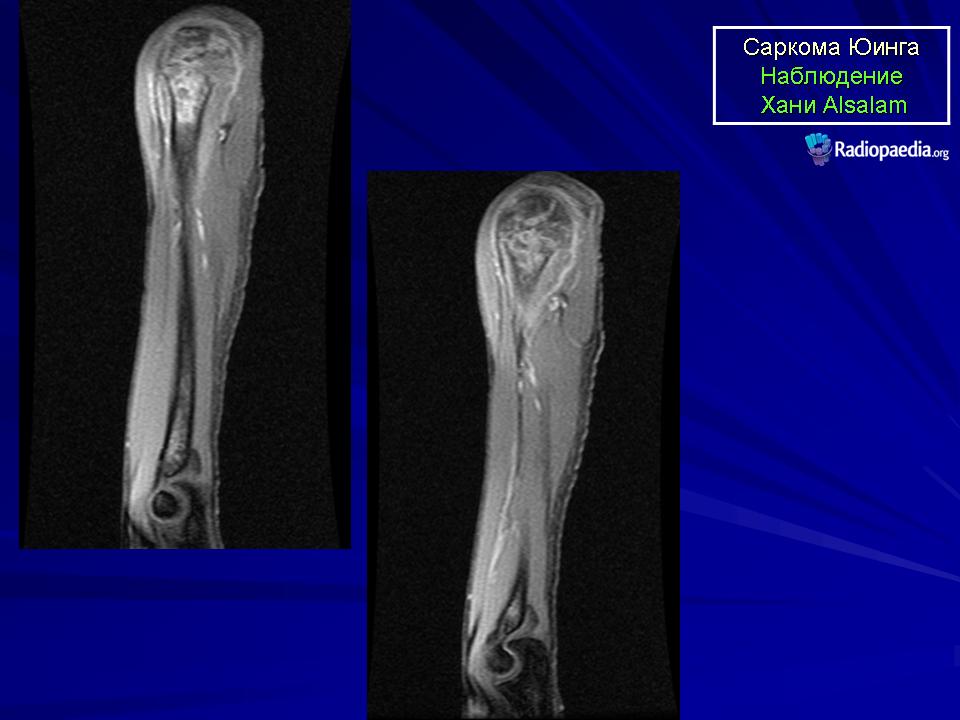

Для установления окончательного диагноза пациенту проводят компьютерную томографию или магнитно-резонансную томография костей и мягких тканей. Кроме того, выполняется ряд исследований для точной оценки характера новообразования.

Данные исследований КТ и МРТ позволят специалистам точно определить размеры новообразования, степень распространенности и поражение близлежащих тканей.

При выявлении типичных рентгенологических признаков саркомы Юинга больного направляют в отделение онкологии, где проводится расширенное обследование для оценки состояния первичного очага и выявления метастазов. В ходе такого обследования выполняется компьютерная томография или магнитно-резонансная томография костей и мягких тканей, пораженных злокачественным процессом.

Данные исследования позволяют точно определить размер новообразования, степень его распространения по костно-мозговому каналу, связь с сосудисто-нервным пучком и окружающими тканями.

Магнитно-резонансная томография (МРТ) дает дополнительную информацию относительно состояния костного мозга, мышц и соединительной ткани вокруг пораженных костей и помогает определить степень распространения опухоли.